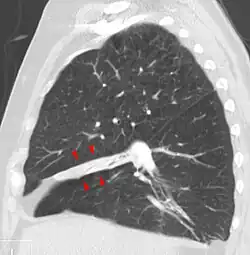

Bei der Perkussion hört man eine Dämpfung des Lungenschalls. Bei der Palpation besteht eine Abschwächung des Stimmfremitus.[3] Das Atemgeräusch ist bei der Auskultation der Lunge abgeschwächt. Im Röntgenbild des Thorax sind als direkte Zeichen eine Transparenzminderung und Verlagerung der Lappenspalten sowie als indirekte Zeichen ein Zwerchfellhochstand, eine Mediastinalverlagerung, ein kompensatorisches Emphysem, eine Hilusverlagerung und eine Engstellung der Rippen zu sehen. Differenzialdiagnostisch muss an eine Pneumonie gedacht werden, Atelektasen zeigen im Gegensatz zu dieser kein Bronchopneumogramm. Alternativ oder ergänzend zum Röntgenbild kann man eine Computertomografie-Aufnahme anfertigen. Im Ultraschall sieht man Atelektasen im Bereich eines Pleuraergusses als nicht belüftete, volumenverminderte Lungenabschnitte.